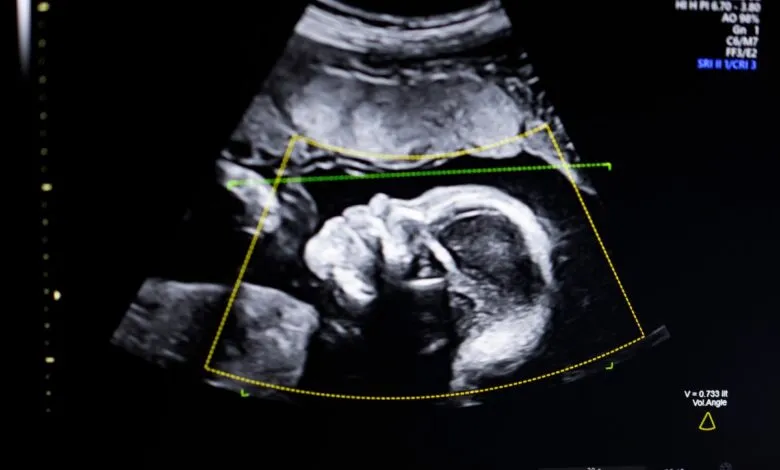

The U.S. Food and Drug Administration has granted clearance to an innovative artificial intelligence software designed to enhance prenatal care. Developed by Biotics AI, this technology analyzes ultrasound images to help clinicians detect fetal abnormalities, assess image quality, ensure anatomical completeness, and automate reporting. This advancement arrives at a critical time, as the United States contends with some of the most challenging prenatal outcomes among high-income nations, particularly for Black mothers who face disproportionately high rates of maternal mortality.

Bustami describes the prenatal ultrasound as the cornerstone of modern pregnancy monitoring, but he notes that the variable quality of images can sometimes lead to misdiagnosis. His team’s software applies computer vision AI to bring greater consistency and insight to this vital process. While building the AI models, trained on a diverse dataset of 11,000 ultrasounds, was complex, Bustami emphasizes that the most difficult challenge was ensuring reliable real-world performance. Proving consistent efficacy across all patient demographics, especially those at highest risk, was an absolute priority.